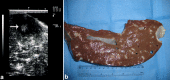

In camels, hepatic diseases are relatively common and most of them are misdiagnosed as a cause of illness because signs may be subtle. In addition, diagnostic laboratory methods are insufficient as hepatic enzymes can also be elevated in camels with cardiac or skeletal muscle damage. Examples of liver diseases in camels are hepatic lipidosis, hepatitis, cirrhosis, hepatic necrosis, choleostasis, hyperplasia of biliary epithelium, hydatid cysts, glycogen deposition, cholangitis, cholangiohepatitis, calcified hydatid cyst and hepatic abscesses. When the liver is examined by ultrasonography, the clinician gets sufficient information about the size, position, echopatterns of the hepatic parenchyma, bile ducts and outlines of the hepatic blood vessels. Ultrasonography has been used previously in camels only for reproductive purposes. However, during the past decade, it has been used for scanning of the healthy organs as well as evaluation and determining the diagnosis and prognosis of non-reproductive disorders. Examples of diseases evaluated by ultrasonography in camels are paratuberculosis, trypanosomiasis, abdominal and urinary disorders, thoracic diseases, renal tumors, pyelonephritis, renal abscessation, gastrointestinal tumors, chronic peritonitis and splenic abscessation. Ultrasound-guidance in biopsy of hepatic lesions and in portocentesis has also been reported in camels. This mini review article is written to shed light on ultrasonography of the liver and its blood vessels in healthy camels as well as finding in camels with hepatic disorders such as fatty infiltration of the liver, hepatic abscesses and calcification of the bile ducts.